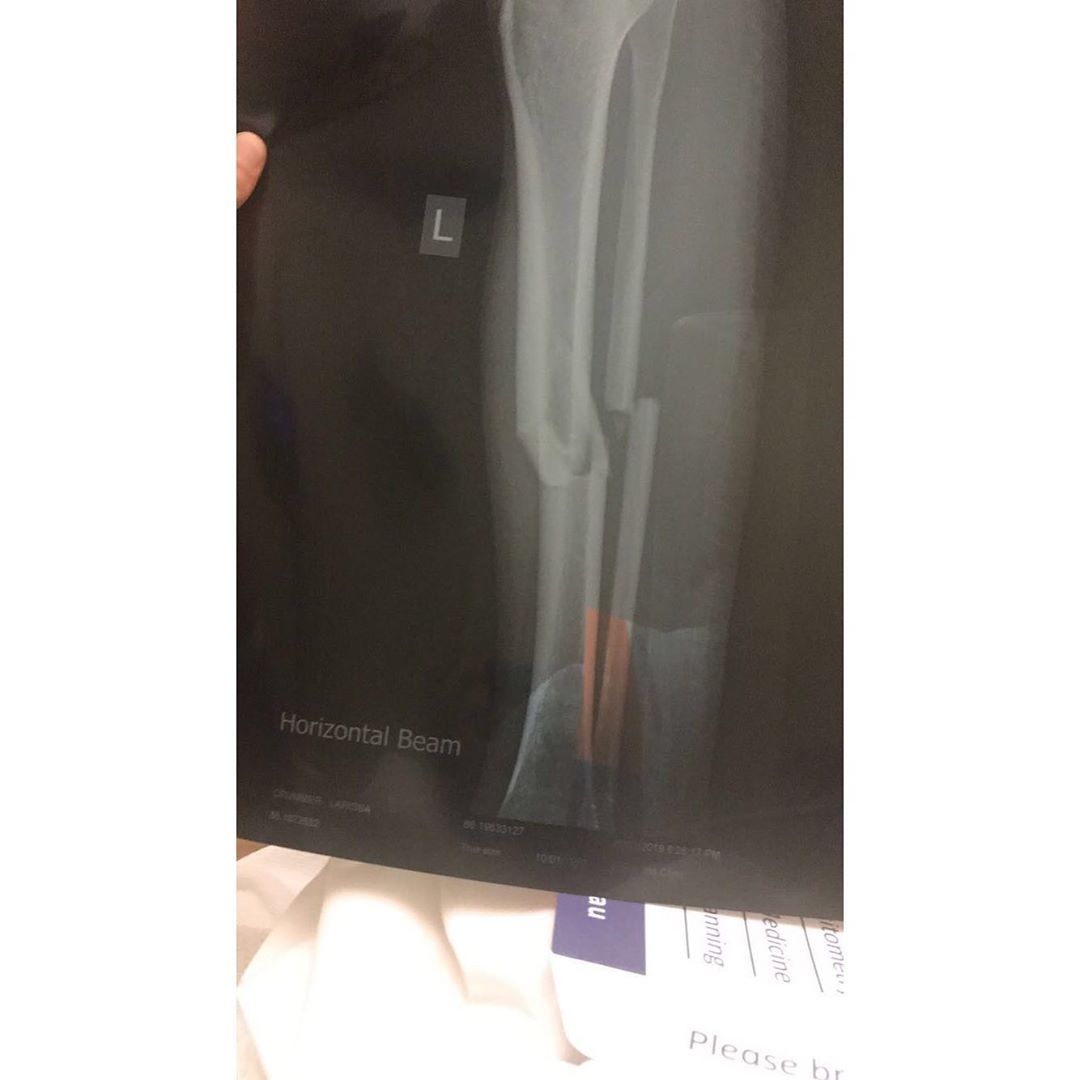

Crummer was later whisked away by ambulance and fears were confirmed when she later revealed she had suffered a broken tibia (shin bone) and fibula (calf bone) in her left leg and required the insertion of a steel rod via surgery.

The surgeon told her that her injury presented like one that had been sustained in a motor vehicle accident and Crummer would be in for a difficult healing process.

Firstly, she suffered with Compartment Syndrome due to the pressure in her leg from blood and fluid. She needed this drained and spent several weeks in hospital with an open leg, waiting for the swelling to go down. It was here that she was told if they had waited any longer to treat her, Crummer could've lost her leg.

Three months later, she suffered a bone infection so it was surgery number three to have her steel rod removed and replaced, and then later, she had to have all the screws in her leg taken out as they were causing discomfort.